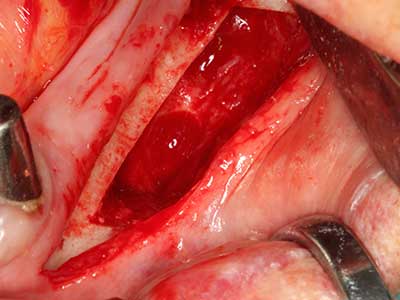

Fig. 1: Preparation of a bone cover with the Piezomed (W&H Salzburg, Austria).

Fig. 3: Basal separation of the block is easier with specially angled attachments.